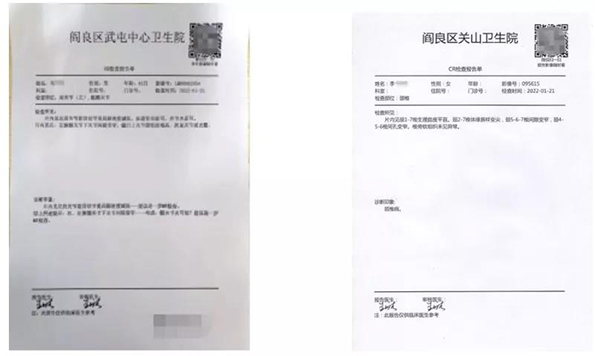

“云”影像,简单地说就是抛弃传统胶片,通过手机、ipad等智能终端查看检查报告和片子。只需微信扫一扫报告单上的二维码,随时随地查阅影像和电子报告,方便携带和保存。如有会诊需求,也可以把二维码拍照发给相关医师,医师只需识别二维码就可以查看病人的检查结果。

图1 检查报告单上附二维码标识